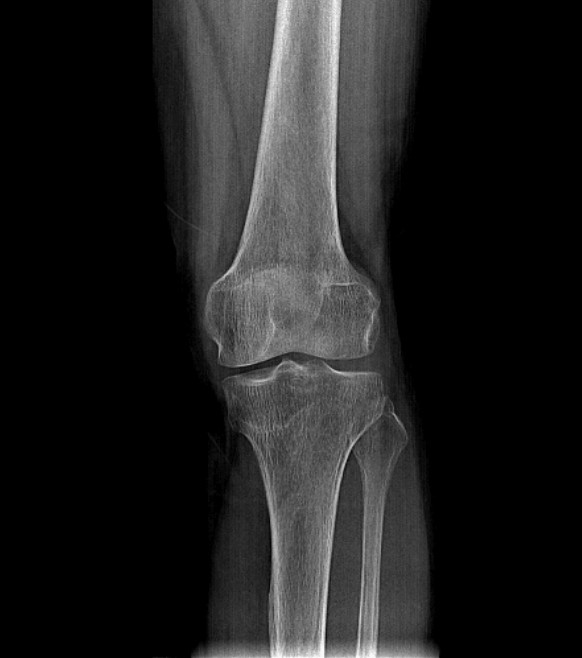

这是因为更强的 X 光意味着更多的 X 射线能够穿透被拍摄物体并到达成像设备。例如,在拍摄胸部 X 光片时,如果 X 光的强度增加,那么肺部等组织在图像中会显得更亮,骨骼等密度较高的结构相对也会更清晰。

然而,需要注意的是,X 光的强度并不是决定图像亮度的唯一因素。被拍摄物体的密度和厚度也会对图像的亮度产生影响。

比如,同样强度的 X 光照射,骨骼的成像会比软组织更暗,因为骨骼对 X 光的阻挡作用更强。

另外,在实际的 X 光拍摄中,医生会根据具体的拍摄部位和诊断需求,合理调整 X 光的强度以及其他参数,以获得最能满足诊断要求的图像。